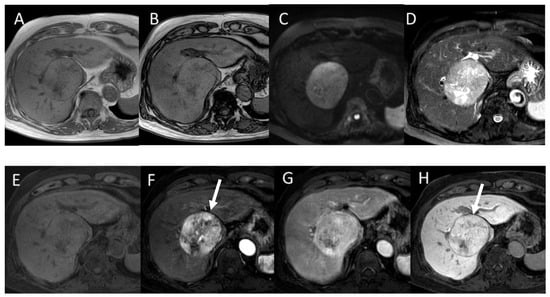

4.7. Combined Hepatocellular and Cholangiocarcinoma (cHCC-CCA)